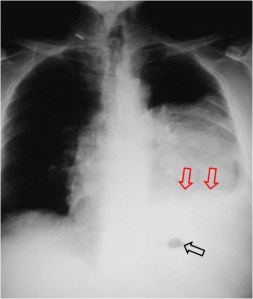

Cuando existe una aparente elevación del hemidiafragma izquierdo pero la burbuja gástrica permanece en su sitio, con el consiguiente aumento de distancia entre la burbuja gástrica y el aparente diafragma, hay que sospechar derrame subpulmonar y no elevación real del hemidiafragma. La fotografía muestra el signo; la flecha negra señala la burbuja gástrica; las flechas rojas marcan el aparente diafragma.

La imagen localizada permite ver mejor, además, el pinzamiento del seno costofrénico izquierdo por el derrame (flecha).